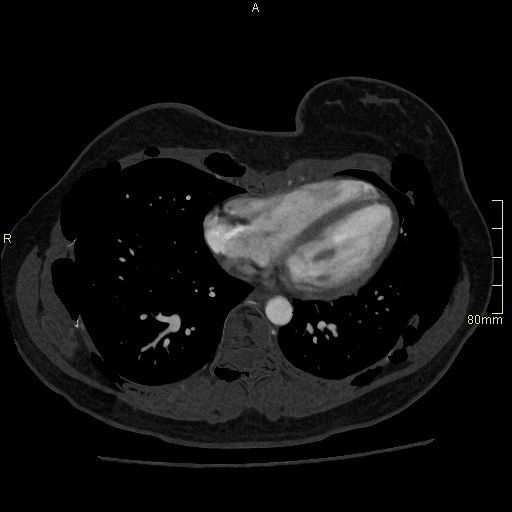

CT Angiography Renal - Maximum Intensity Projection (axial)

CT Angiography Renal - Subtraction (axial)